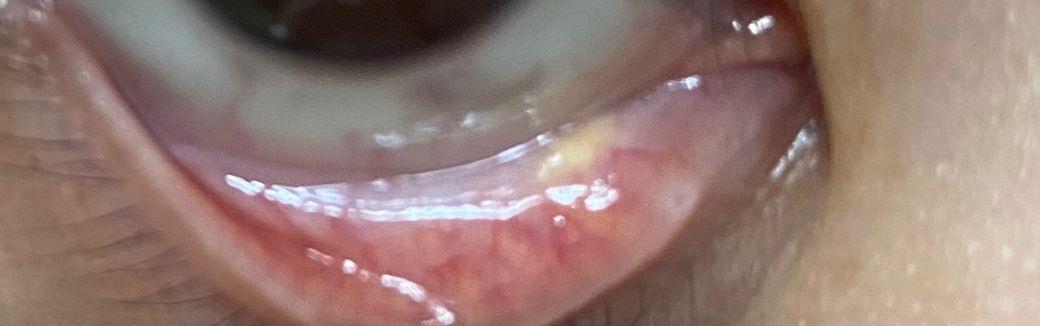

눈 아래 꺼플을 내리니까 기름 덩어리가 오른쪽 눈이 있는데

오른쪽 눈 밑에 까니까 노란 기름 같은 덩어리? 이런게 있는데 이게 뭔가요??? 아프거나 하는건 없는데 한쪽에만 있어서요 없애는 방법이 있나요??